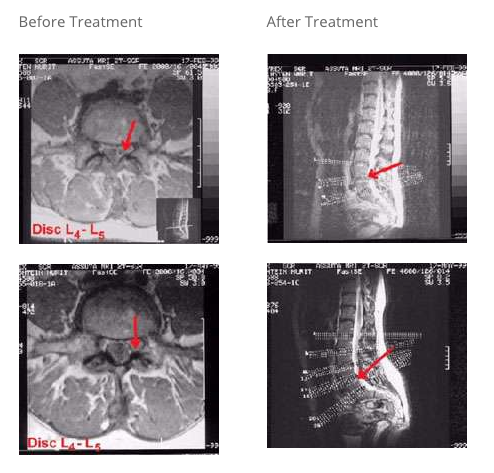

Case Study:

Patient: 47-year-old female with acute low back pain, severe sciatica with left side radiation, and neurological symptoms. Imaging displayed severe left neural foraminal herniation of the disc (red arrow above) causing stenosis with mild cord pressure.

Plan of Care: Two weeks of daily treatment sessions with the Vertetrac, followed by 2 months of treatments every other day.

Results: Patient has no further complaints of pain, sciatica, or neurological symptoms. The MRI shows no herniation of the disc, with only a mild residual edema of the left root. No apparent spinal cord pressure.